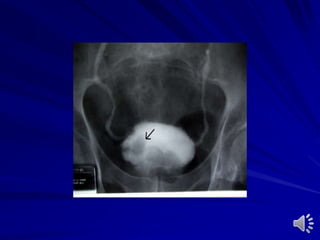

Cystography

Ascending And Micturating Cystourethrography Catheterin the urethra and fill it with contrast medium Catheter in the bladder and fill it with contrast medium Indications: – Trauma – Vesicoureteral reflux – Posterior urethral valve – Stricture urethra – Stress incontinence – Fistula